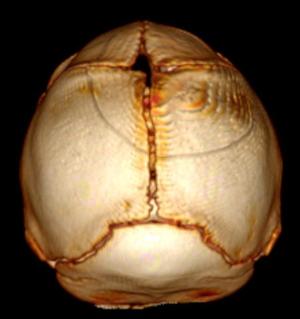

In a third study, ultrasound and fetal MRI were performed on pregnant patients with Zika virus infection at different gestational ages. Once the babies were born, they underwent ultrasound, CT and MRI. The researchers then created 3-D virtual and physical models of the skulls. More than half the babies had microcephaly, brain calcifications and loss of brain tissue volume, along with other structural changes.

"The emergence of Zika virus in the Americas has coincided with increased reports of babies born with microcephaly," said study author Heron Werner Jr., M.D., Ph.D., from the Department of Radiology at Clínica de Diagnóstico por Imagem. "An early diagnosis may help in treating these babies after birth. Moreover, the knowledge of abnormalities present in the central nervous system may give hints about the pathophysiology of the disease."